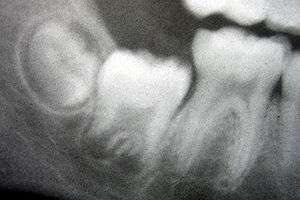

A: enamel

B: dentin

The adjacent layer of cells in the dental papilla suddenly increases in size and differentiates into odontoblasts, which are the cells that form dentin.[24] Researchers believe that the odontoblasts would not form if it were not for the changes occurring in the IEE. As the changes to the IEE and the formation of odontoblasts continue from the tips of the cusps, the odontoblasts secrete a substance, an organic matrix, into their immediate surrounding. The organic matrix contains the material needed for dentin formation. As odontoblasts deposit organic matrix termed predentin, they migrate toward the center of the dental papilla. Thus, unlike enamel, dentin starts forming in the surface closest to the outside of the tooth and proceeds inward. Cytoplasmic extensions are left behind as the odontoblasts move inward. The unique, tubular microscopic appearance of dentin is a result of the formation of dentin around these extensions.[1]

After dentin formation begins, the cells of the IEE secrete an organic matrix against the dentin. This matrix immediately mineralizes and becomes the initial layer of the tooth's enamel. Outside the dentin are the newly formed ameloblasts in response to the formation of dentin, which are cells that continue the process of enamel formation; therefore, enamel formation moves outwards, adding new material to the outer surface of the developing tooth.